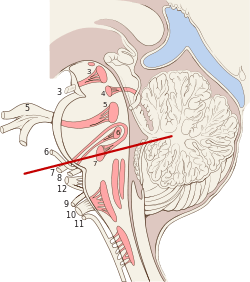

Diagram showing the positions of the three principal subarachnoid cisternae (pons visible at center) | |

Median sagittal section of brain Nuclei of the pons and brainstem

Nuclei of the pons and brainstem- Cerebrum. Deep dissection. Inferior dissection.